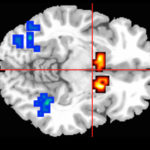

Poiché YAP / TAZ sono attivi in ​​molti tumori, comprese le forme aggressive di cancro al seno e alla vescica, i ricercatori si sono chiesti se anche NUAK2 fosse elevato nelle biopsie tumorali prelevate da pazienti con carcinoma della vescica. Hanno scoperto che NUAK2 era presente ad alti livelli in alcuni dei tumori che provenivano da pazienti il ​​cui cancro progrediva verso un tipo più aggressivo.

Bloccando la proteina NUAK2, sia attraverso farmaci che mutando il gene che la codifica, i ricercatori sono stati in grado di rallentare l’espansione delle cellule del cancro al seno in un piastra di Petri e di ridurre i tumori al seno nei topi, rispettivamente. Un approccio simile potrebbe mirare a tumori di alto grado nei pazienti.